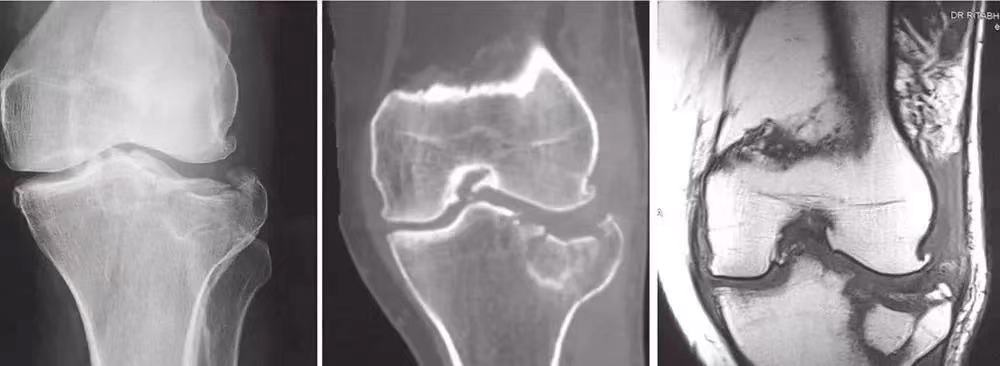

(6)胫骨髁骨折

股骨髁部骨折:暴力强大,压痛点在股骨髁部,X线片示股骨髁骨折。